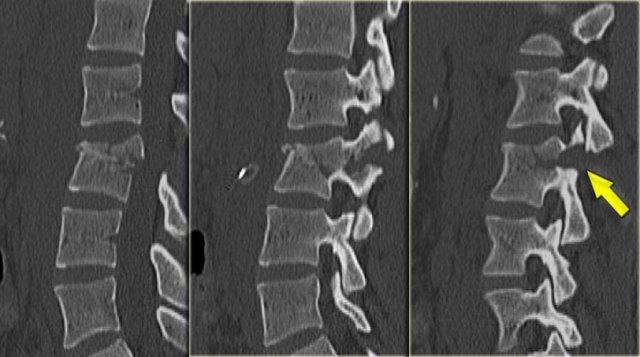

Ở bên trái là hình ảnh của một nữ bệnh nhân 21 tuổi nhập viện sau chấn thương do dây an toàn.

Bệnh nhân đã được phẫu thuật thăm dò ổ bụng để sửa chữa vết rách tá tràng.

Không có thiếu hụt thần kinh.

Trước tiên hãy nghiên cứu các hình ảnh, sau đó tiếp tục đọc.

Những gì chúng ta thấy là một ví dụ điển hình của gãy xương Chance, đây là tổn thương ba cột với hướng nằm ngang của đường gãy.

Tiếp tục với các hình ảnh CT.

Điều đặc biệt của gãy xương Chance là hướng nằm ngang, được thể hiện rõ ràng trên các hình tái tạo mặt phẳng đứng dọc ở bên trái.

Tiếp tục với các hình tái tạo mặt phẳng đứng ngang.

Cũng trên các hình tái tạo mặt phẳng coronal, chúng ta có thể thấy hướng nằm ngang của đường gãy.